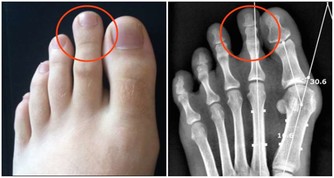

骨質疏鬆、肌肉力量差、平衡能力差。

俗話說“人老先老腿”是很有道理的,實際上從40歲開始,人的肌肉每年都在不斷地往下衰減,

那麼如果肌肉力量不足以支撐行走就會出現步態異常。

很多老年人步基很寬,如果平衡能力又不好的話就很容易跌倒。

為什麼肌肉減少了就容易跌倒呢?

專家介紹,因為骨骼只起到支撐身體的作用,是肌肉控制骨骼和關節的活動,

只有依靠肌肉帶動骨骼運動,人體才能自由活動。

很多老年人的腿部無法伸直,不論是因為骨質增生還是肌肉無力,結果就是膝關節受力不均勻,從而導致走路不穩、打軟腿等,這也是很多老年人摔倒的原因。針對這類情況,老年人可以做伸膝鍛煉。

醫學上將0~30度的區間稱為終末伸膝鍛煉,用來專門鍛煉大腿部的股內側肌。

根據研究發現,老年人的肌肉萎縮大多從股內側肌開始,所以老年人可以多做一些終末伸膝鍛煉,預防和改善肌肉萎縮,防止摔倒。